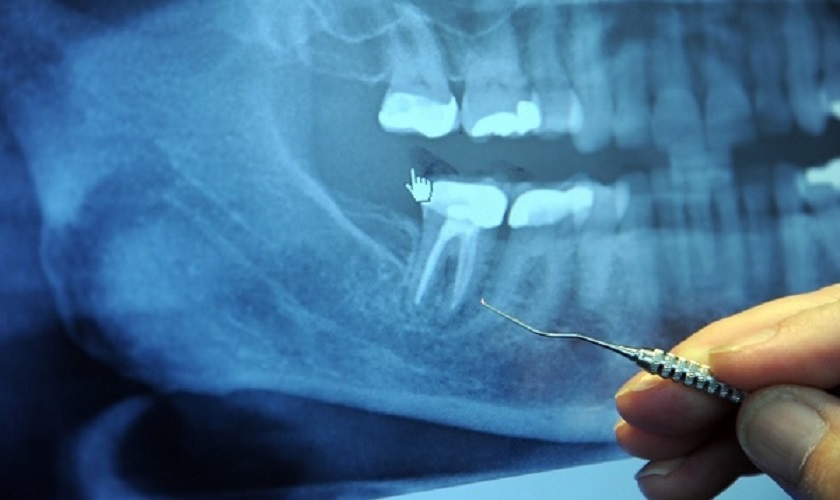

Trước khi quyết định có nên lấy tủy răng không, bạn cần được thăm khám răng và chụp X – quang. Thông qua phim chụp, bác sĩ sẽ quan sát và định vị khu vực viêm, đánh giá mức độ viêm để tư vấn, lên kế hoạch điều trị cụ thể cho từng khách hàng.

Chụp X – quang để đánh giá tình trạng răng trước khi điều trị